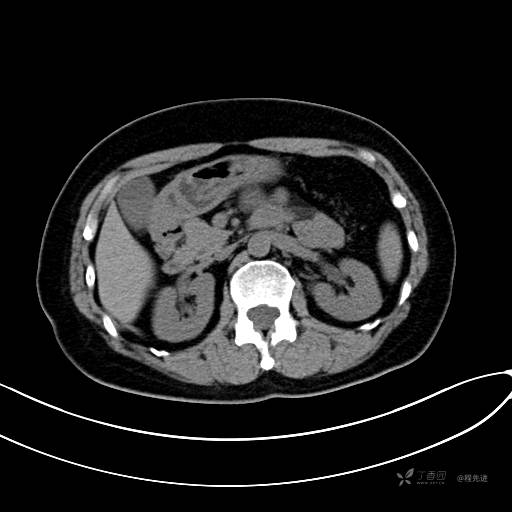

CT增强门脉期